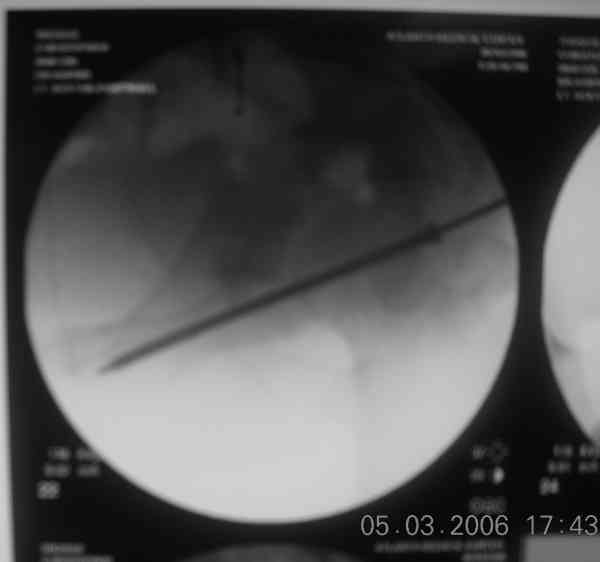

Prone

Here's a pic from the foot of the bed and you can see the clamp in the wound and the knee is extended so he must've had a tight rectus. The C-arm is rolled back to an obturator oblique image to reveal the anterior column...we put a slight outlet tilt to combine the images and give a better view of the anterior column...we can see the posterior column limb reduction in the wound, we can palpate the quadrilateral surface limb, and the image demonstrates the anterior column portion...you can adjust the tilt and rotation to image tangentially to the fracture plane if you'd like. We've inserted a 2mm K wire to site the starting point and aim/orientation for the drill and screw

Prone Imaging

same image, just another look.

Prone Inlet

OK, now we're inserting the drill percutaneosuy using a sleeve. This fluoro shot is not for this patient (notice no clamp) but I was too lazy to go searching the PACS for one with the clamp on, so pretend...I'll save the next ones and send along...the imaging is the same and the clamp doesn't obstruct imaging other than very rarely...you can always tilt the C-arm a bit to clear it if the clamp obstructs the exact spot that you'd like to see. We'll assume that everyone knows the safe zone for a medullary ramus screw. Use a calibrated drill and sleeve of known length to simplify your life...or use Alex's fancy cannulated screws...I like 3.5mm screws because the oscillating 2.5mm drill bounces and remains intraosseus when it oscillates and contacts endosteal cortical ramus... so will the screw, and like a long bent screw IF the fracture is clamped... if unclamped, when the screw contacts the endosteum, it pushes the reduction apart instead of bouncing. The big 7mm cannulated screws fit few patients and extrude...we very rarely use them any more...you'll see an old one later.